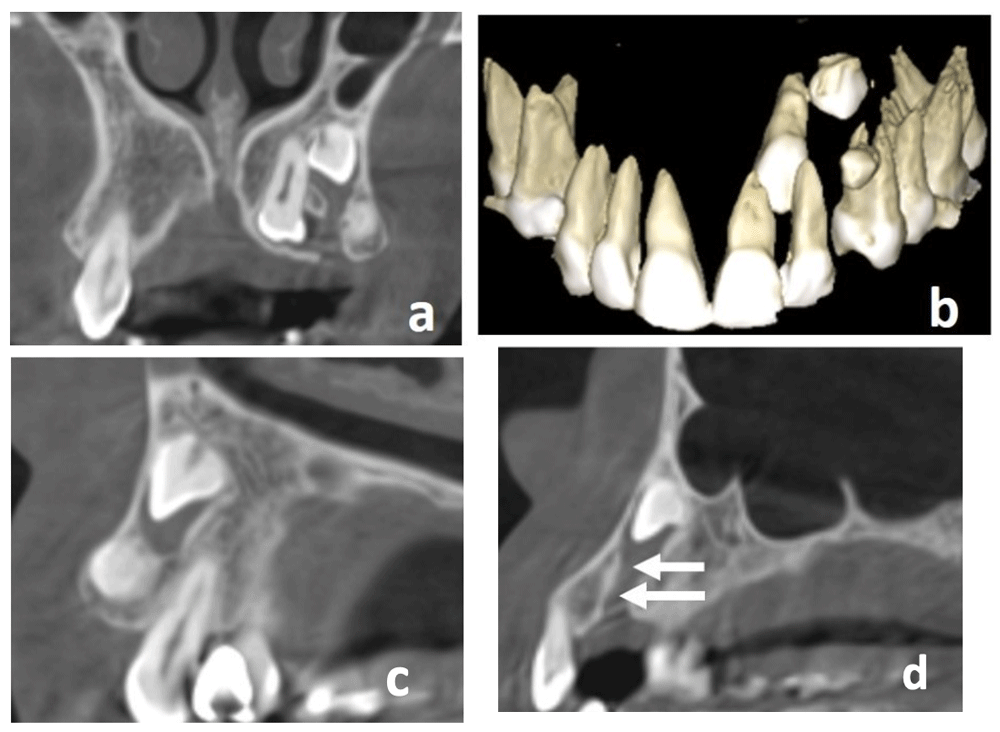

CBCT showed that tooth #23 was palatally impacted between teeth #21 and #22. There was a very small well defined rounded denticle like mass positioned distal to tooth #22 and coronal to the impacted supernumerary tooth (crown only), causing a small clinical buccal bulging and preventing its eruption. (Figure 2a, b, c).

a) Coronal cone-beam computed tomography (CBCT) scan showing impacted left maxillary canine, supernumerary tooth and odontoma with continuous follicular space b) Three-dimensional CBCT reconstruction showing palatal impacted maxillary left canine together with supernumerary tooth and odontoma c) Sagittal CBCT scan showing odontoma occlusal to supernumerary tooth d) Sagittal CBCT scan showing the proposed gubernacular canal (white arrow).

The sagittal CBCT slice showed radiographic evidence of continuity of the follicular space of the supernumerary tooth along the bone up to its most inferior part at the alveolar ridge. This was determined to most likely be the gubernacular canal as it followed its possible eruption pathway through the bone. However, the denticle like structure was located inside this pathway and prevented the eruption of the supernumerary tooth. (Figure 2d)

The role of gubernacular cord (GC) and the canal in tooth eruption is not clear, although it has been suggested that it may have a central role in inducing normal tooth eruption as it constitutes a pathway from the dental follicle to the gingiva for the eruption of permanent teeth11. Oda M. et al.24 suggested that the presence of and contact with the gubernacular tract (GT) should be added as a characteristic CT finding of some types odontogenic masses including dentigerous cysts, calcifying odontogenic cysts (Gorlin Cyst), odontomas, Adenomatoid Odontogenic Tumor and perhaps others. Moreover, they concluded that dentists should pay more attention to the association between the GT and odontogenic masses24,25. Our case demonstrated an association between the GT and the odontoma where the odontoma was inside the GT of the supernumerary tooth with the same spatial relationship in agreement with Oda M. et al.24 which reports that the majority of odontoma cases (about 70%) detected with CBCT were inside the GT of the unerupted teeth (Figure 2d). Furthermore, during surgery, it was apparent that the GT was contiguous with the supernumerary follicle, suggesting that the GT was guiding the eruption of the supernumerary tooth, but the development of the odontoma prevented its eruption. Gaˆeta-Araujo H et al. reported that the most communal attachment site of GC was to the occlusal side of the dental sac of the unerupted tooth (93.2%) and was classified as a usual attachment. These findings were in agreement with our case, where we also found the GT to be attached to the occlusal aspect of the dental sac of the supernumerary tooth25.